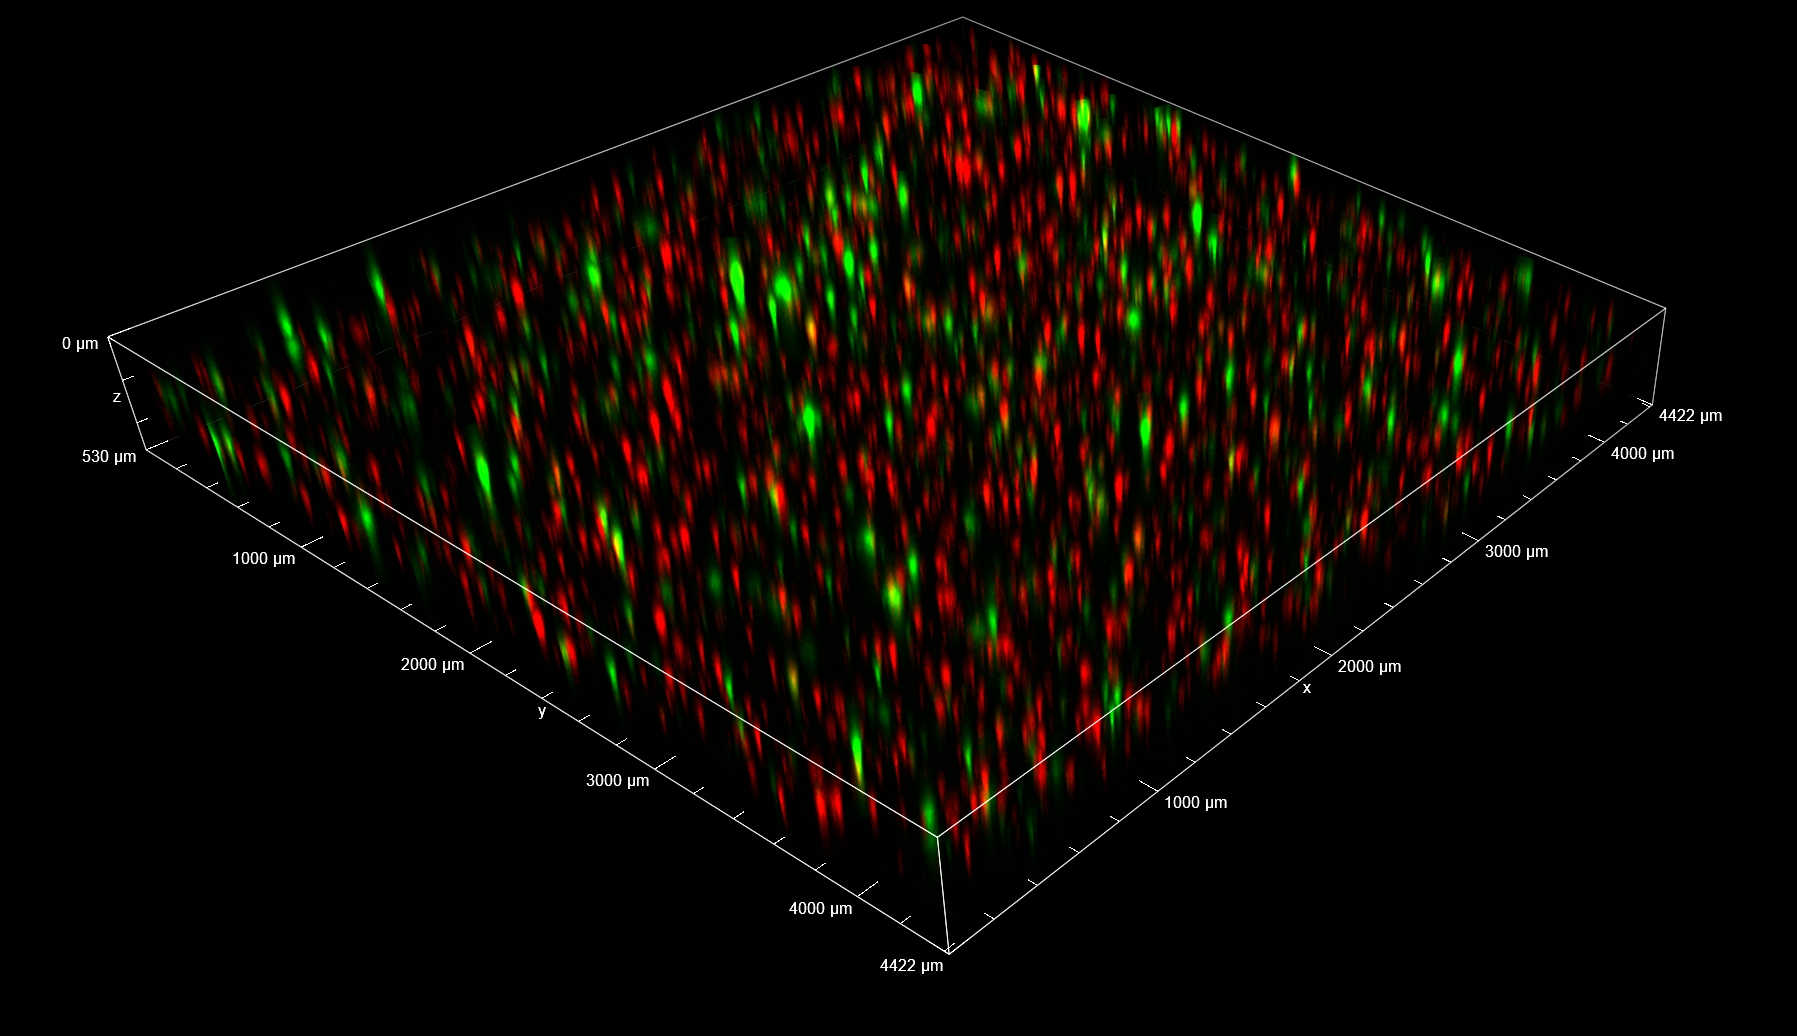

In the Figure 2, the full field of view (FOV) in XYZ dimensions collected 24 h post-treatment is shown. Thanks to the 25 mm diagonal FOV of the camera and to the ability to penetrate inside the sample without losing the spinning disk confocality, it was possible to visualize and record cells that homogeneously colonize the entire thickness of the 3D matrix.

Figure 2. 3D view of the entire FOV acquired with spinning disk at 24 h post-treatment. FOV with XY=4422×4422 µm, Z=530 µm. 3D matrix thickness was entirely acquired. Tumor target A673 cells are shown in red and AD-MSCs TRAIL in green.